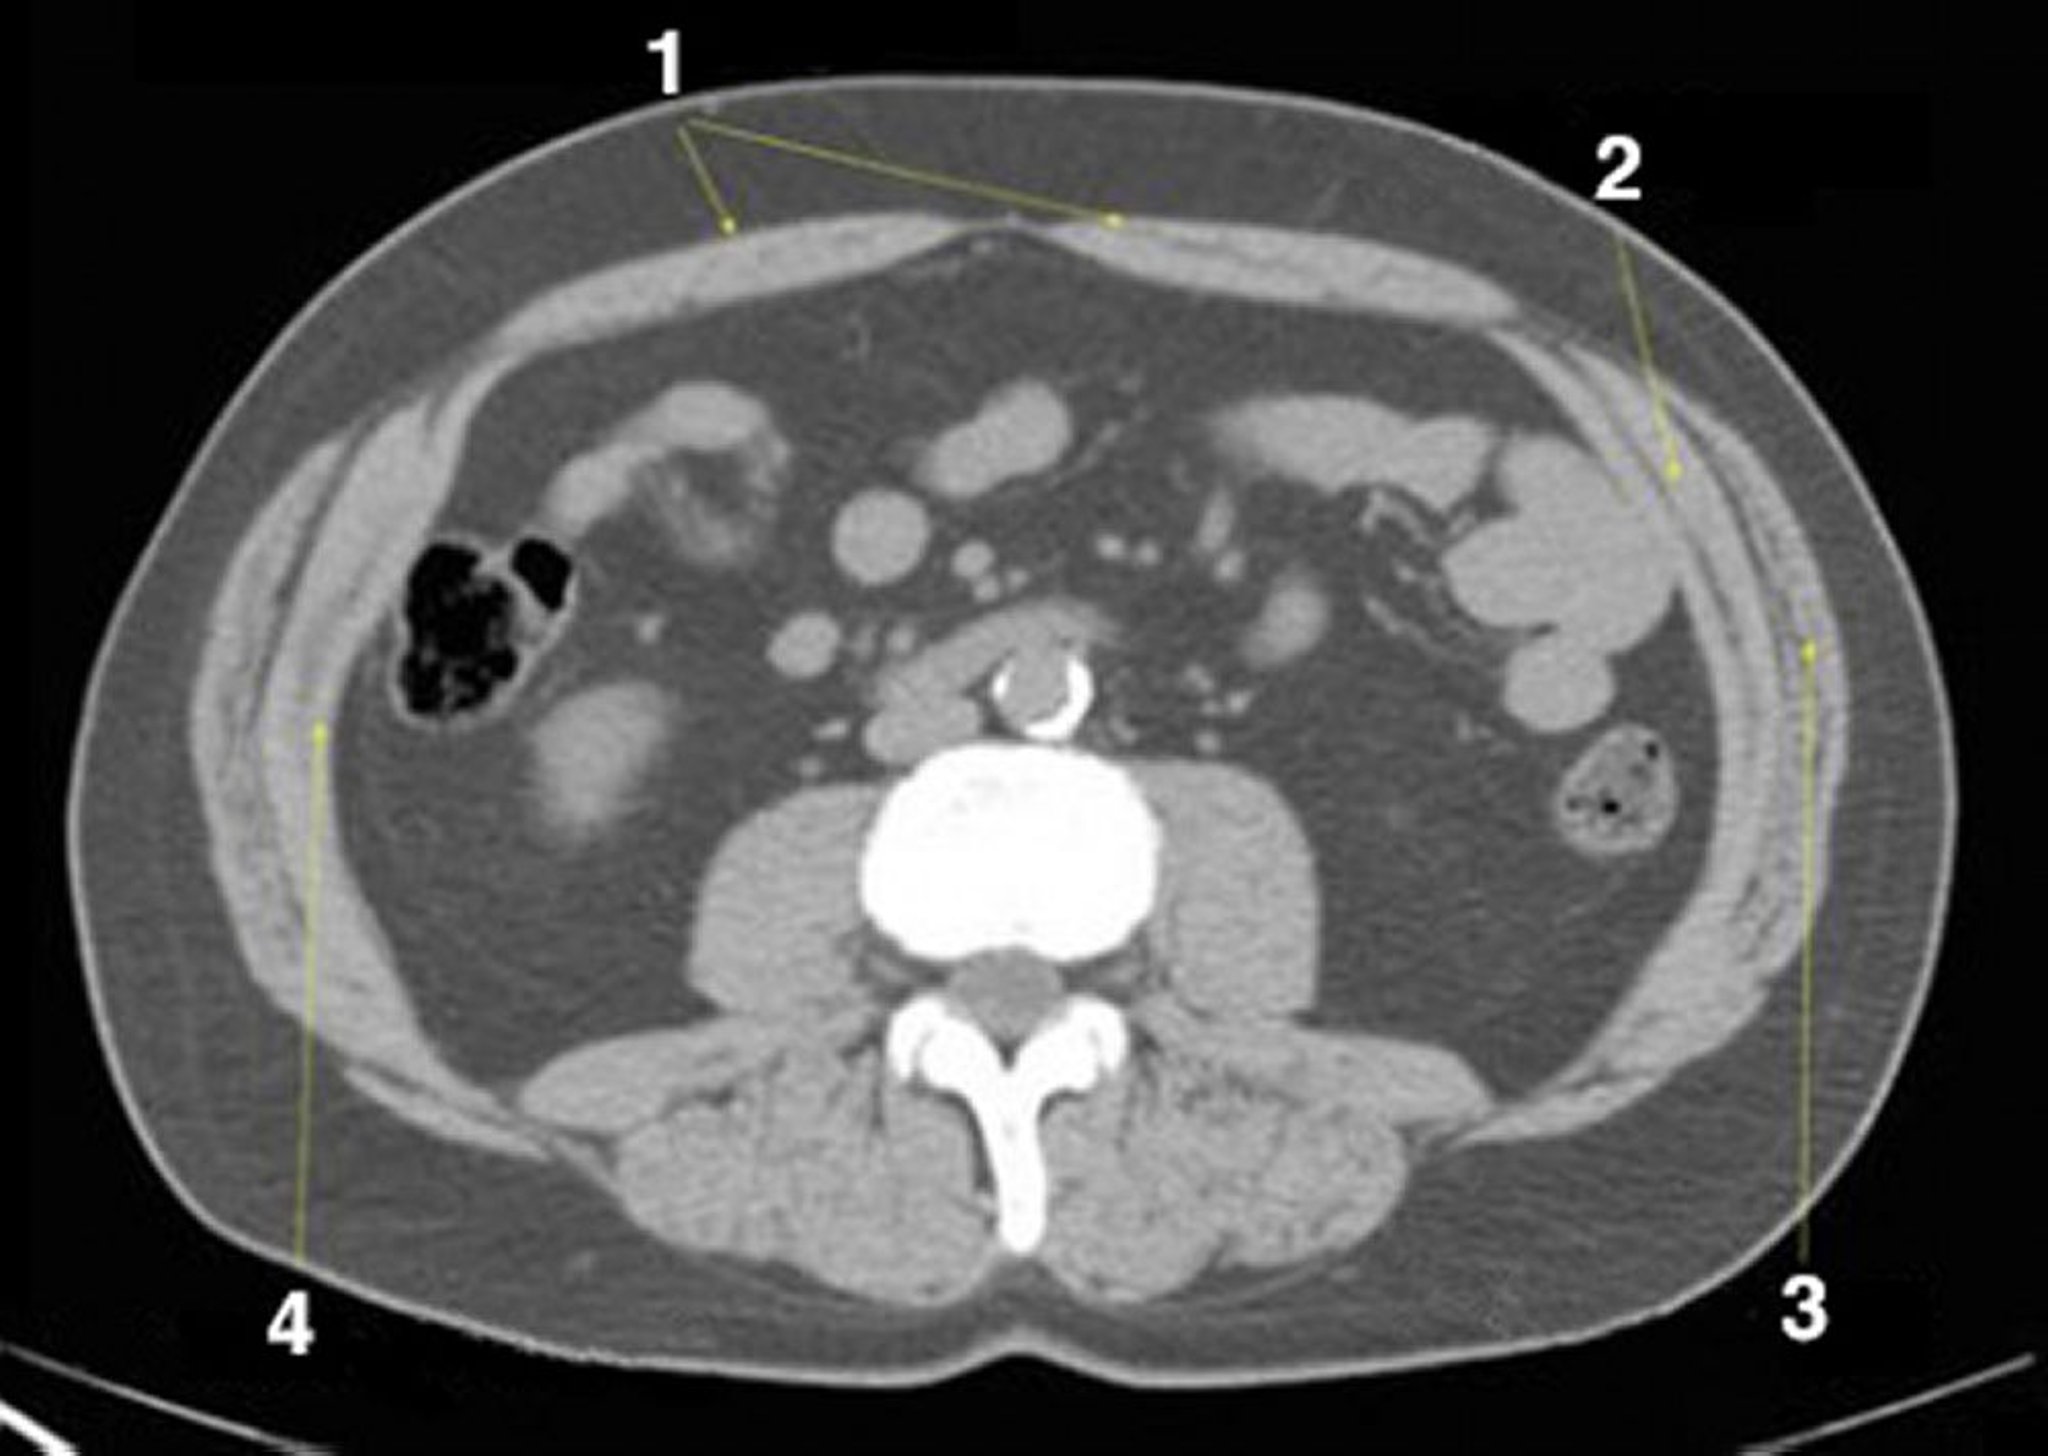

正常解剖を示した腹部および骨盤の単純CT画像(スライド19)

1 = 腹直筋;2 = 内腹斜筋;3 = 外腹斜筋;4 = 腹横筋。